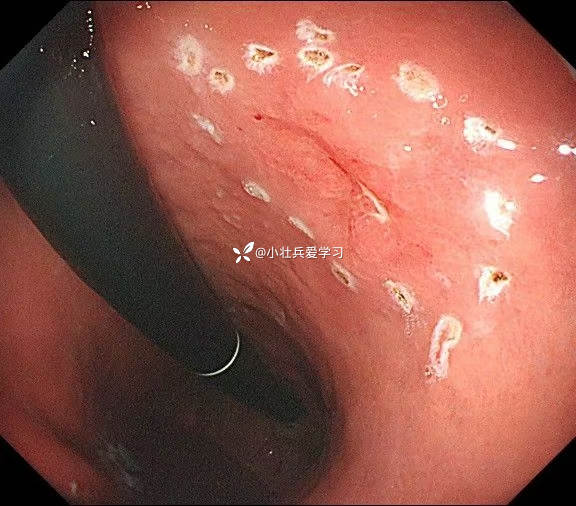

临床诊断:溃疡型胃角早癌

术前谈话诊断性ESD

术后病理示粘膜内癌(M3期),切缘阴性,达到治愈性切除标准,术后不用再追加外科手术、放化疗,对病人来说是不幸中的万幸。